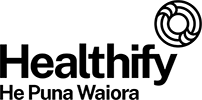

Respiratory diseases

Respiratory diseases are conditions that affect any of the processes involved with breathing. If you or someone you know are one of the 1 in 6 New Zealanders that lives with a respiratory condition, here you can find some useful information on how to manage the condition well.